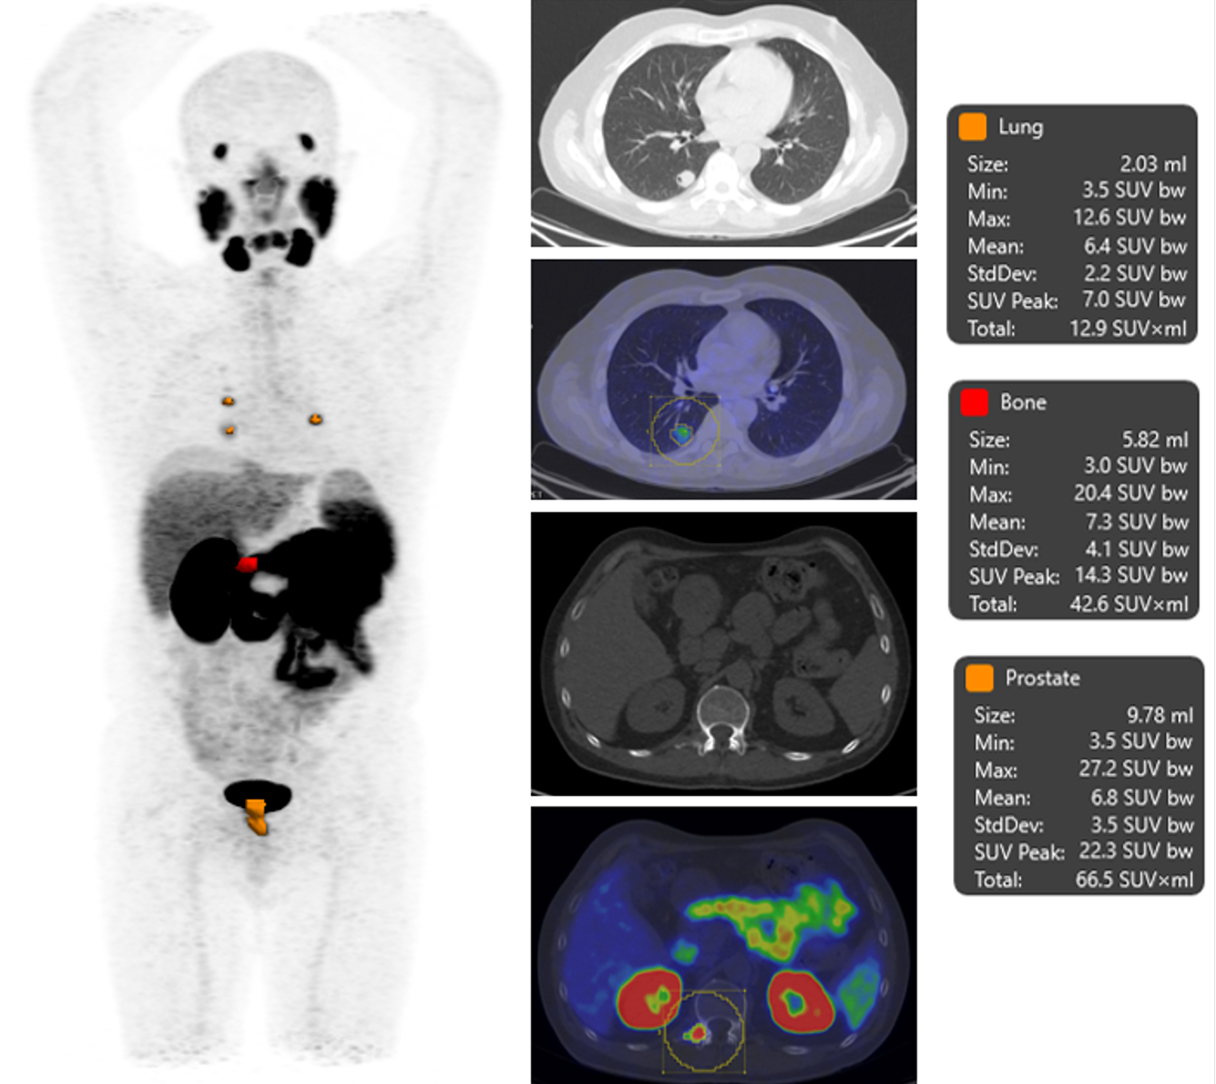

There is a world outside the stent mesh

Caso condiviso da Saima Mushtaq

Paziente con anamnesi di malattia coronarica e pregresso impianto di stent sulla discendente anteriore sinistra.